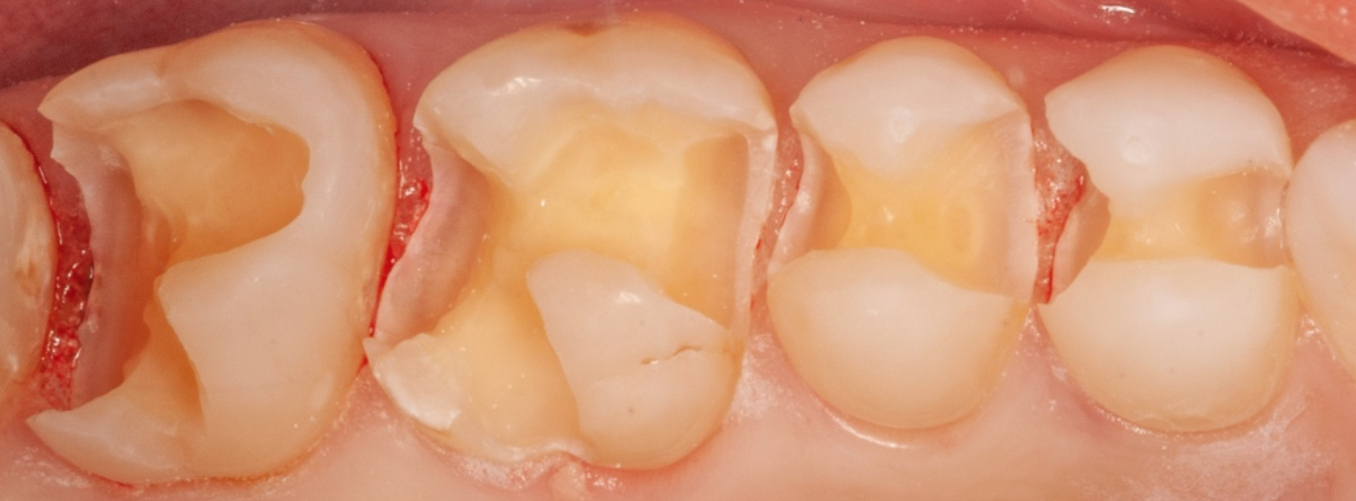

The below is of a woman in her mid-30’s who came to us as a new patient, wanting to be proactive and address early signs of oral disease before becoming serious issues. During the New Patient Experience, we showed her photographs and xrays of her upper right posterior teeth, with old failing “fillings”, and she was concerned.

After much discussion, and showing her photographs of prior cases utilizing the minimally-invasive technique, she chose the Maximized Adhesive Dentistry (MAD) protocol. After administering local anesthetic, we excavated all the old failing fillings and resulting tooth decay, preserving all the healthy enamel that remained.

We then removed all debris and contaminants, thoroughly disinfected the teeth, and incrementally built back and sculpted with composite… no crowns, no root canals. Truly a great example of where art and science meet in the practice of dentistry! This quadrant of the mouth was restored in one long morning appointment.